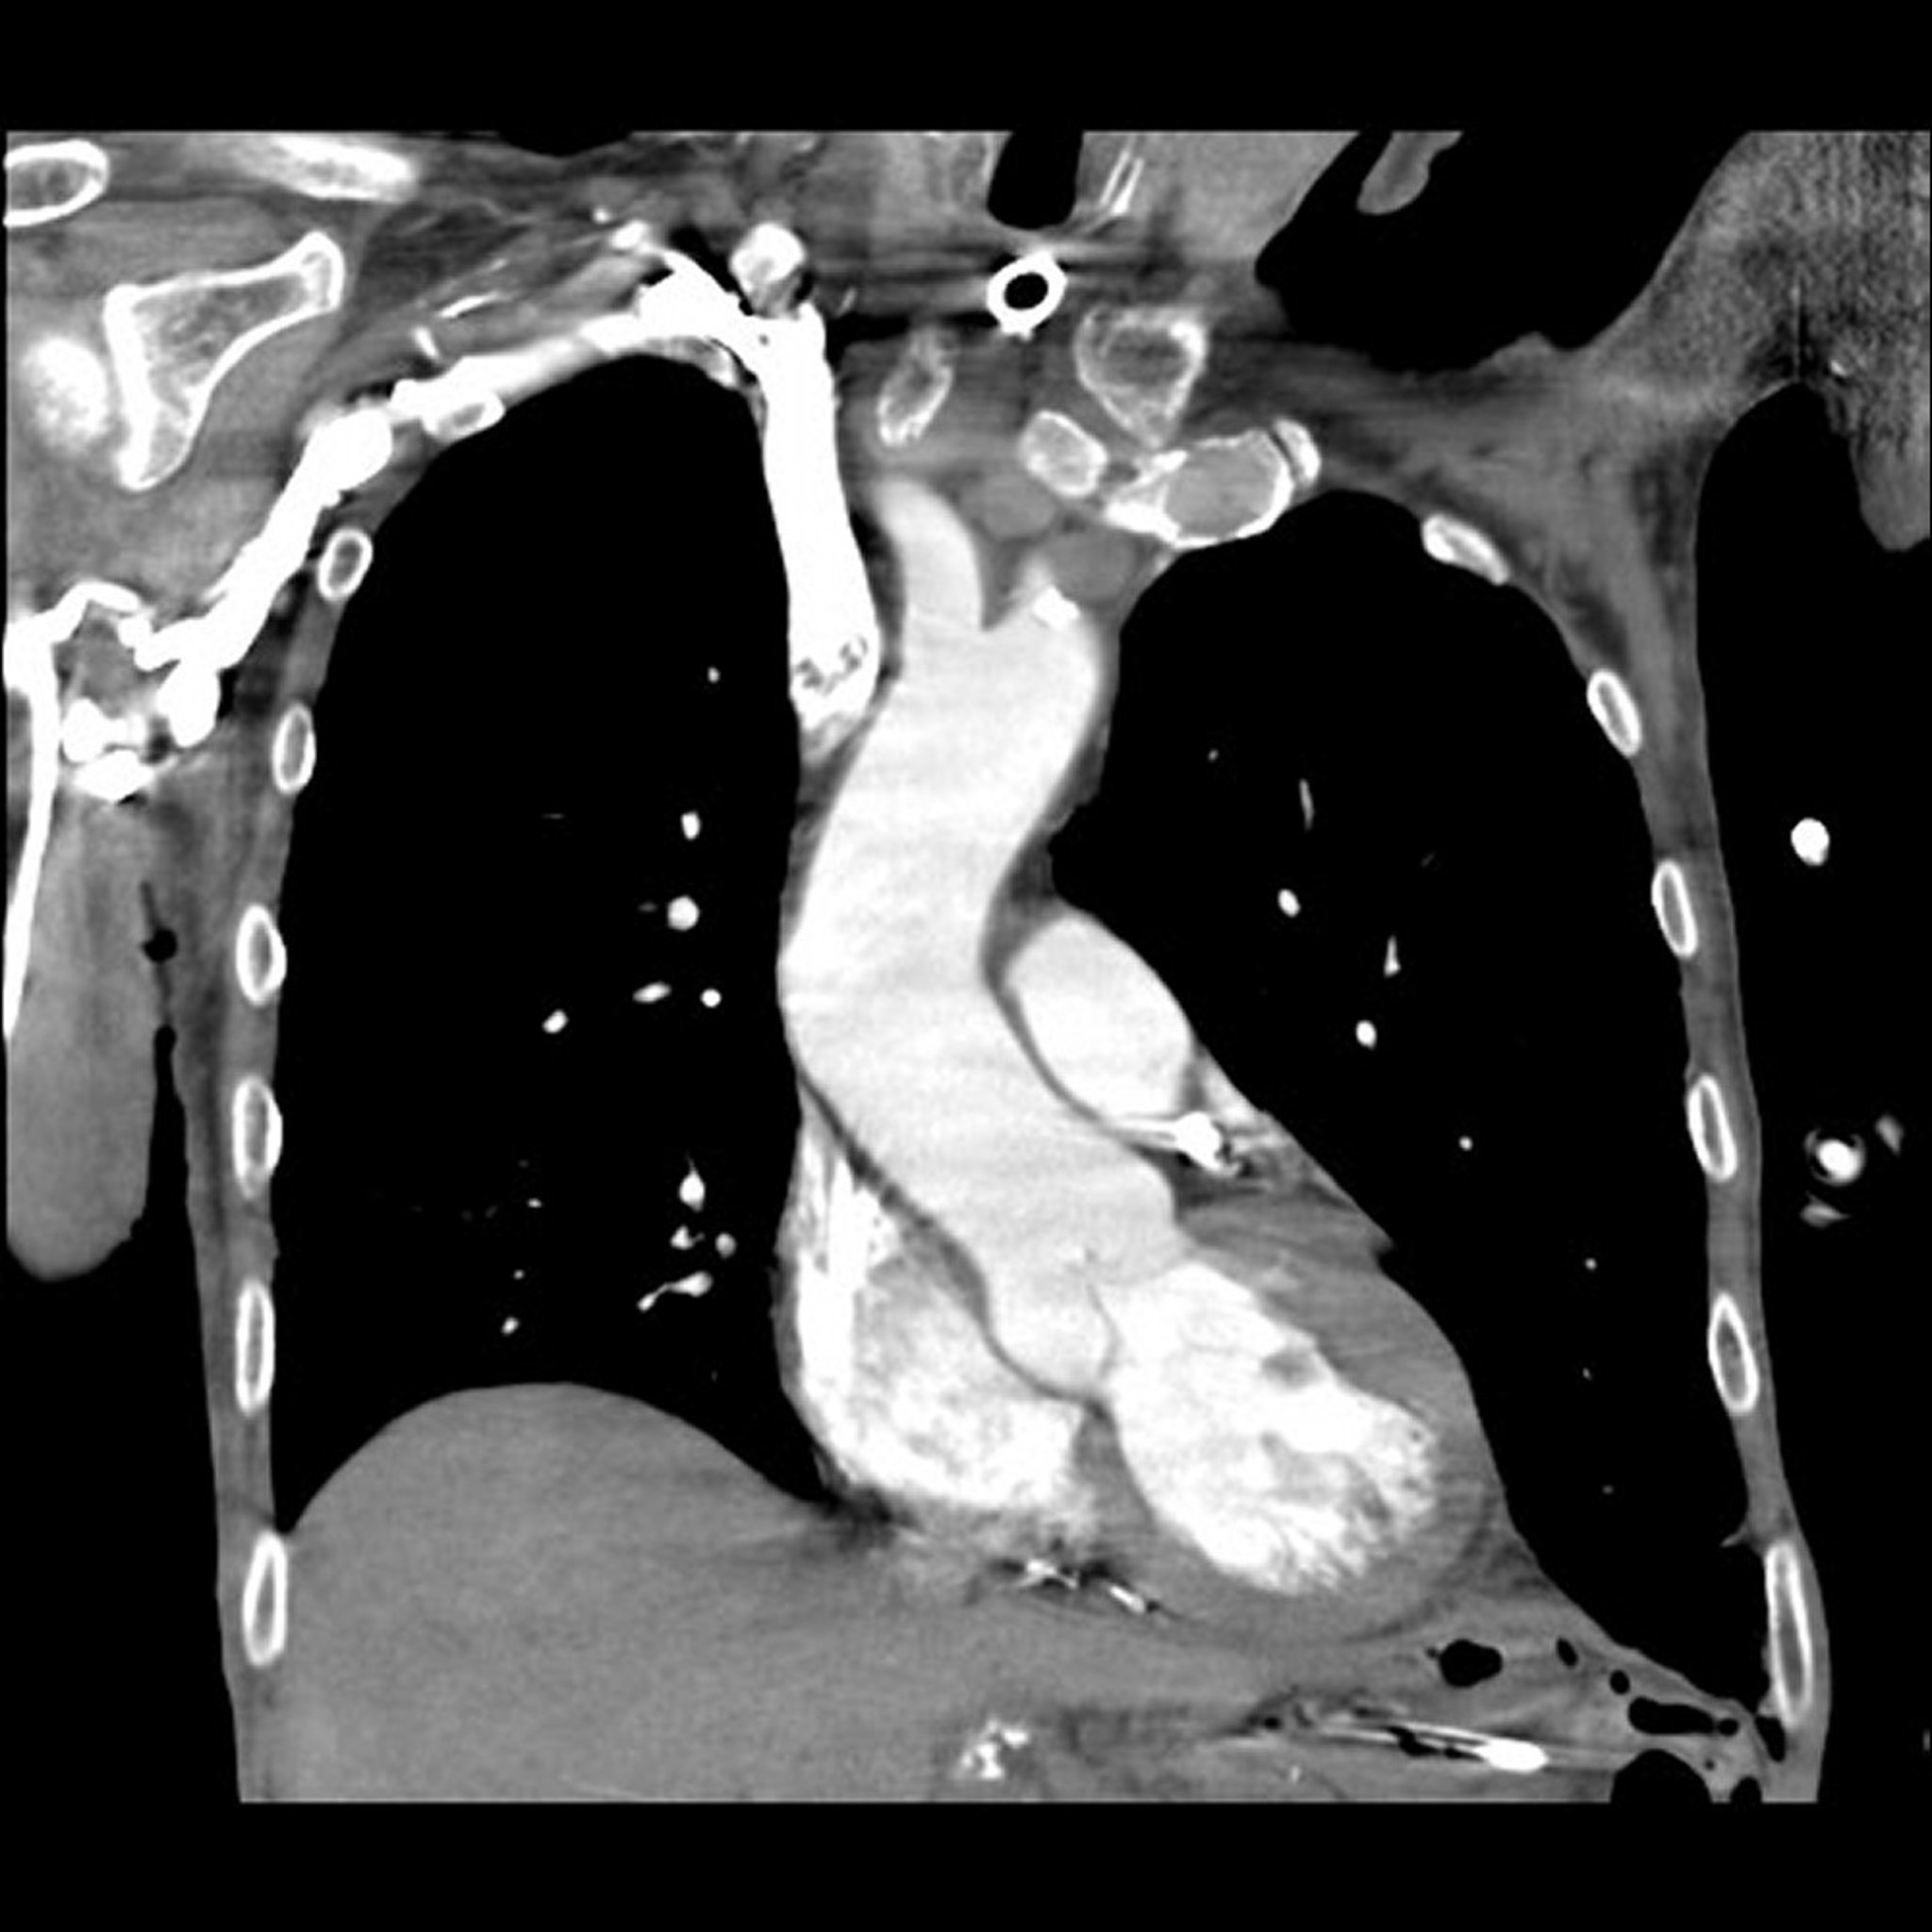

Angiografi CT

Angiografi CT menggunakan CT dan agen kontras radiopak untuk menghasilkan gambar 2 dan 3 dimensi pembuluh darah, termasuk arteri yang memasok jantung (arteri koroner). Agen kontras diinjeksikan ke dalam vena (bukan arteri seperti pada angiografi konvensional), biasanya di lengan. Gambar diambil dengan cepat dan terwaktu sehingga menunjukkan agen kontras radiopak yang mengalir melalui pembuluh darah yang sedang dievaluasi. Komputer secara digital menghapus semua jaringan kecuali pembuluh darah dari gambar. (Lihat juga Angiografi Koroner.)

Angiografi CT digunakan untuk mendeteksi hal berikut:

• Penyempitan atau penyumbatan (seperti pembekuan darah) di arteri

• Tonjolan (aneurisme) dan robekan (diseksi) di arteri besar

• Tidak normalnya pembuluh darah yang membawa darah ke tumor

Angiografi CT umumnya digunakan alih-alih angiografi konvensional karena aman dan tidak terlalu invasif (tidak memerlukan penyisipan kateter ke dalam arteri, yang memiliki risiko sedikit lebih besar dibandingkan penyisipan kateter ke dalam vena). Angiografi CT menunjukkan ketidaknormalan pada pembuluh darah yang sama akuratnya dengan angiografi resonansi magnetik, tetapi sedikit kurang akurat dibandingkan angiografi konvensional.

Angiografi CT biasanya hanya membutuhkan waktu 1 hingga 2 menit.